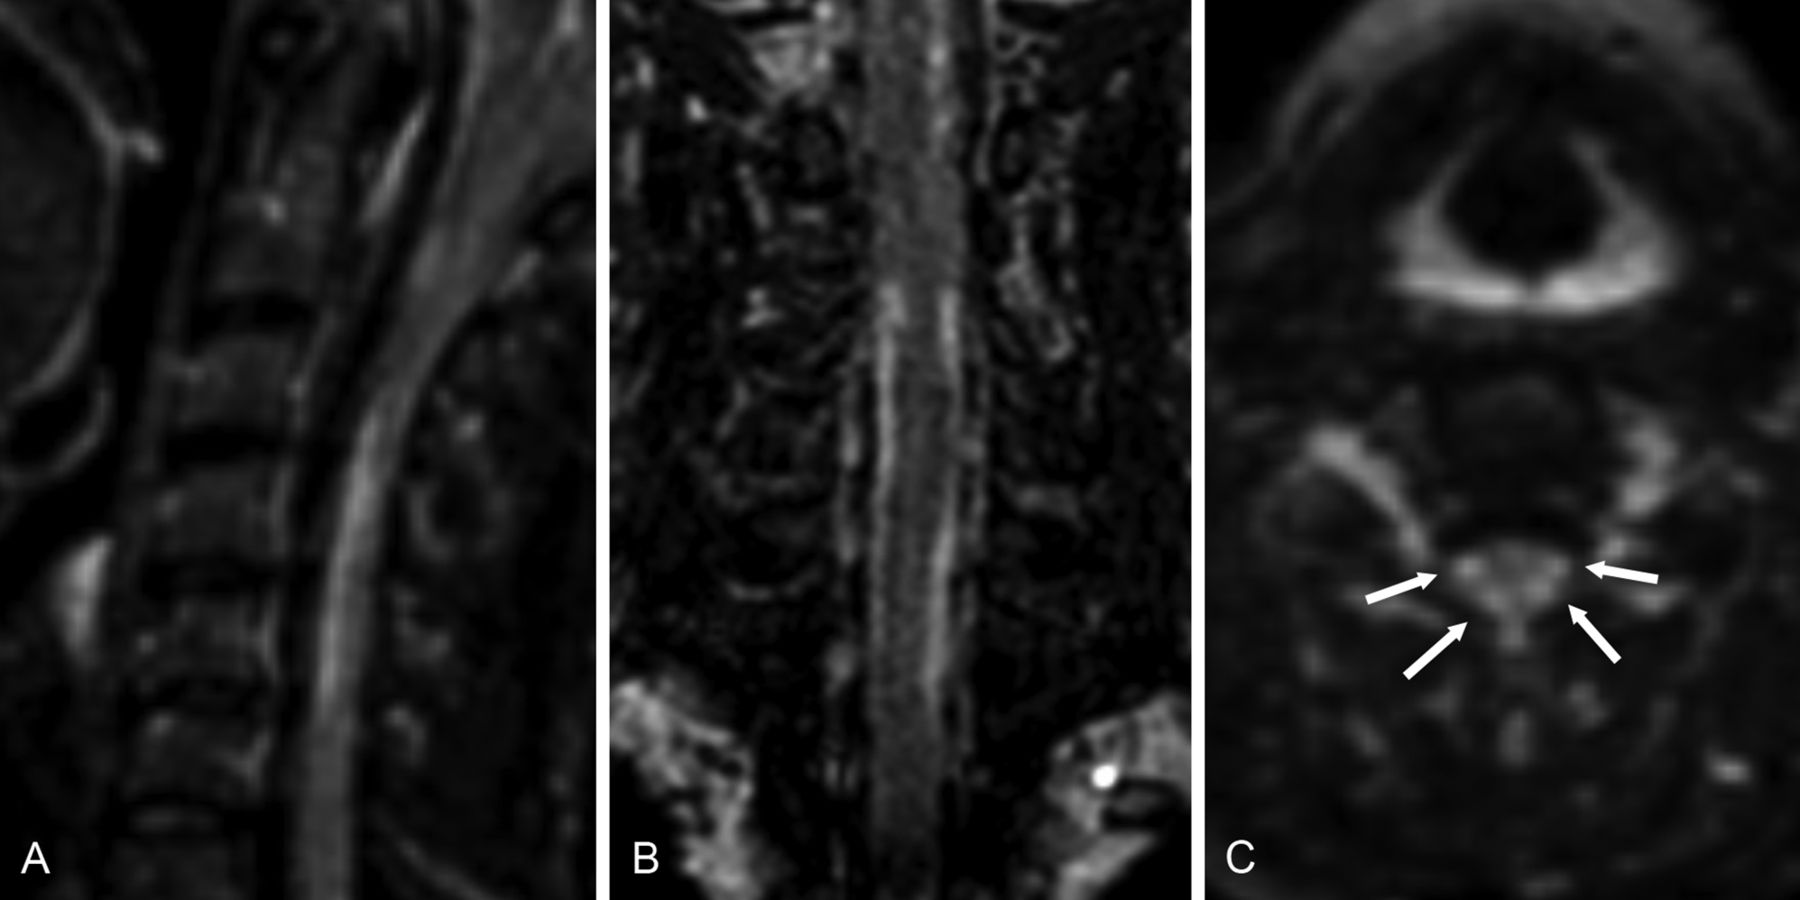

In addition, the benefits of the 3D DIR sequence are likely not to be confined to improved lesion-detection rates. The high sCNR, in combination with high isotropic spatial resolution and the possibility of generating multiplanar reconstructions from a 3D dataset (eg, coronal planes, which are not commonly acquired in routine spinal MR imaging of patients with MS), may allow a more precise delineation of lesion borders, in particular of complex, elongated lesions and small lesions adjacent to the CSF (Fig 5). As one consequence, we would expect the 3D DIR sequence to provide a more precise tool for volumetric measurements than conventional 2D T2WI TSE sequences, which are prone to inaccuracies due to partial volume effects and lower contrast. This expectation, however, needs to be confirmed by additional studies.

Sagittal (A), coronal (B), and axial (C) reconstructions of 3D DIR images of the cervical spinal cord of a 42-year-old female patient with primary-progressive MS. Elongated lesions in the lateral spinal cord are visible on both sides (arrow).